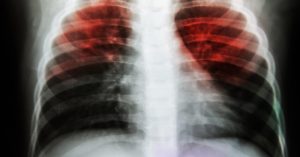

Tuberculosis: It is an infectious disease of the lungs caused by bacteria. Th e disease is communicable, that means it spreads from one person to another through droplets in cough or sneeze.

Pneumonia: It is an inflammatory infection of the air sacs in one or both lungs. Fluid or pus gets filled in the sacs leading to cough with phlegm or pus. It may also cause symptoms like fever, chills and difficulty in breathing. It can be caused by many organisms like bacteria, viruses and fungi.